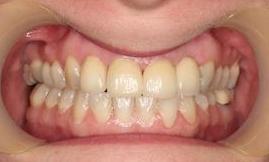

This young dad had four congenitally missing upper teeth. He had a quick orthodontic treatment and a large span bridge placed in as a teenager. He never smiles with teeth showing.

After many years of wear and tear, some of the work started to break and fail. We removed the defective bridges, managed to save all the existing teeth and placed four implant supported crowns in. The patient is very happy to be able to smile confidently now.